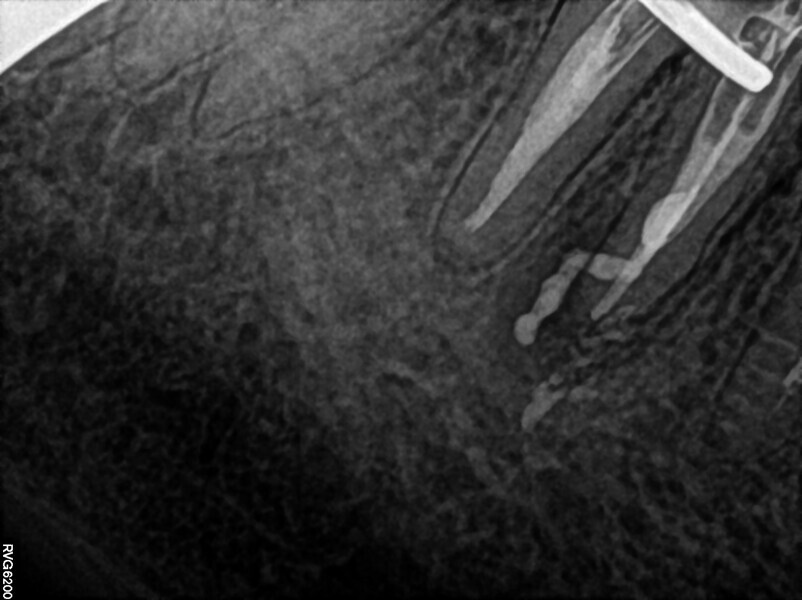

The patient was referred to Dr Witkowski’s dental office for removal of a broken file in the mesial canal and the final endodontic procedure (Fig. 9). Owing to difficulties and the risk of perforation, bypassing of the file was suggested to the patient and she agreed. Proper instrumentation was performed in both the mesial and distal aspects using the R25 RECIPROC blue (VDW; Fig. 10). After this step, extensive irrigation protocol was performed with sonic agitation and continuous irrigation (Fig. 11). The root canal system was then prepared for obturation and obturated using the piston technique (Fig. 12). This technique is capable of obturating even not mechanically instrumented spaces and is very easy to use, especially when there is an obstacle in the canal space such as a broken file (Fig. 13).